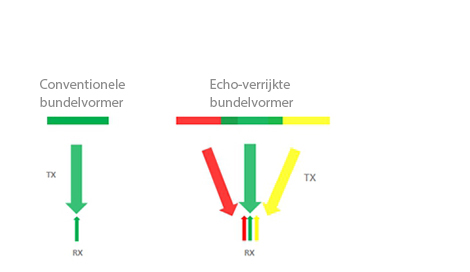

Echo-verrijkte bundelvorming

Met de echo-verrijkte bundelvormer kunnen de gewoonlijk genegeerde echosignalen van aangrenzende bundels worden gebruikt om een fijnere en sterkere beeldvormingsbundel te vormen, met een betere 'buiten-de-focusŌĆÖ-beeldresolutie en diepere beeldpenetratie.